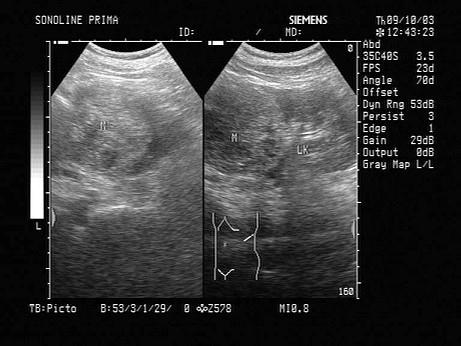

男性,60岁,无痛性血尿,腰部疼痛,该病例最可能的诊断?(?)A.肾错构瘤B.肾脏局灶性炎症C.肾周围脓肿D.肾脏肿瘤E.肾母细胞瘤

问题 男性,60岁,无痛性血尿,腰部疼痛,该病例最可能的诊断?(?)

选项 A.肾错构瘤 B.肾脏局灶性炎症 C.肾周围脓肿 D.肾脏肿瘤 E.肾母细胞瘤

答案 D